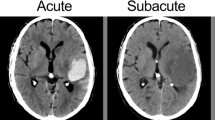

Each MRI examination was reviewed by a board-certified neuroradiologist blinded to the diagnosis. The site of the hematoma was classified as cerebral lobar, basal ganglia, or posterior cranial fossa. Hematomas were classified as acute (isointense or minimal low-signal on T1- and marked low signal on T2-weighted images) or early subacute (high signal on T1- and marked low signal on T2-weighted images).

On the axial T2-weighted image on which the hematoma was visually assessed to be largest, its mean diameter was determined by taking the average of its longest diameter and its diameter perpendicular to that (Fig. 1). In a few cases, a T2*-weighted image was used to help define the margin of the hematoma, but measurements were made on the T2-weighted image. On that same image, vasogenic edema (VE) was measured as the maximum distance from the edge of the hematoma to the peripheral margin of high signal. We defined the VE ratio as follows: VE ratio(%)=(maximum width of edema÷mean diameter of hematoma)x100. Thus, if the width of the zone of vasogenic edema is half the mean diameter of the hematoma, the VE ratio is 50%.

Method for quantifying vasogenic edema around a hematoma. On the axial T2-weighted image in which the hematoma appears largest, its mean diameter is determined as the average of its greatest diameter and its orthogonal. Vasogenic edema is measured on the same image as the maximum distance from the edge of hematoma to the periphery of the margin of high signal around it (x). The VE ratio, expressed as a percentage, is: (maximal width of edema÷mean diameter of hematoma)x100%